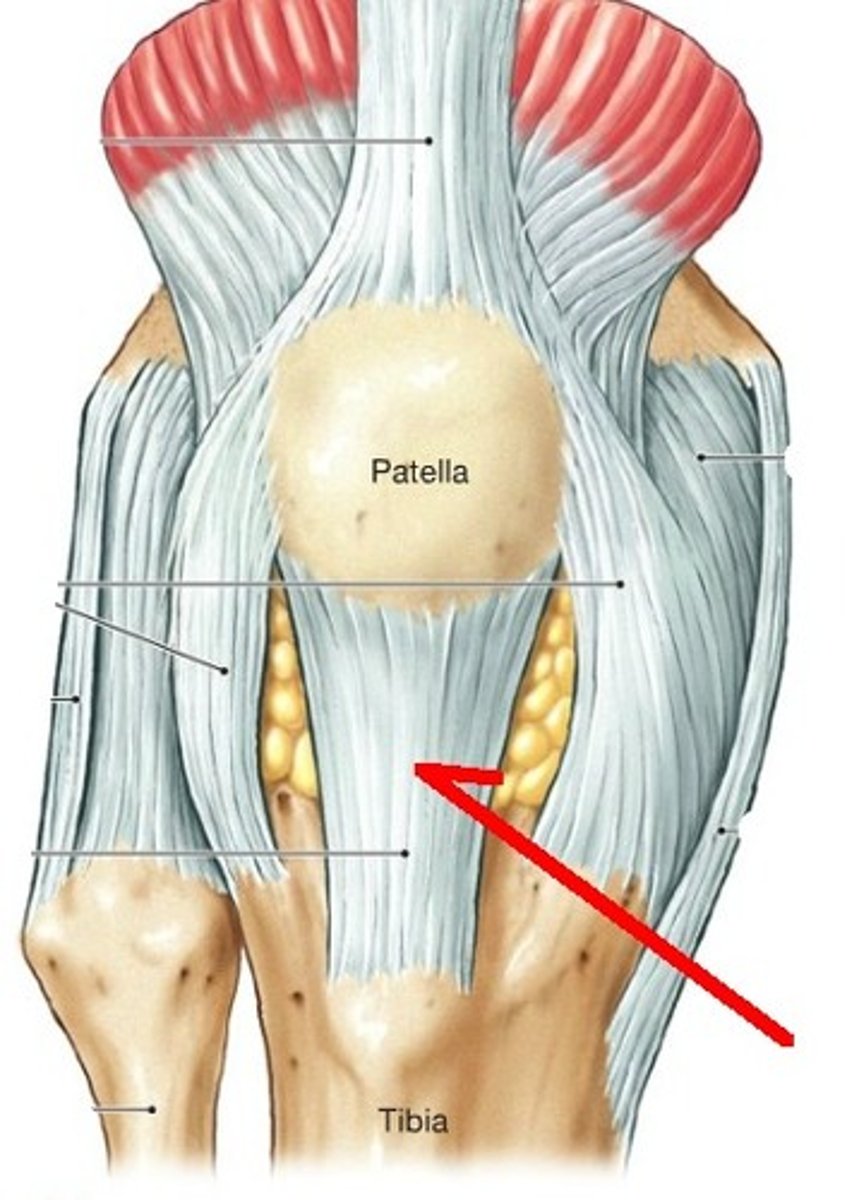

Tendon of Quadricepts

patella

Patellar Ligament

Fibular collateral ligament

Lateral Meniscus

Tibial Collateral Ligament (MCL)

Medial Meniscus

Unhappy trio

MCL, ACL, Medial meniscus